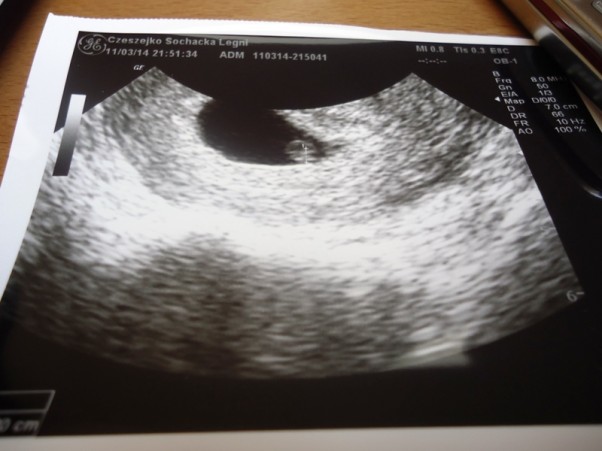

Kiedy? Najchętniej już, teraz, zaraz, dzisiaj! No ale wiadomo to za wcześnie, trzeba czekać! Ale jak? Gdy ja taka niecierpliwa:) Ale doczekałam się 11 marca poleciałam jak na skrzydłach.

Zgadza się, bez wątpienia: "JEST PANI W CIĄŻY"-usłyszałam, a mój uśmiech na twarzy gdy zobaczyłam te malutką kropeczkę, mówił wtedy wszystko. Już kochałam te moje 3mm SZCZĘŚCIA!!!